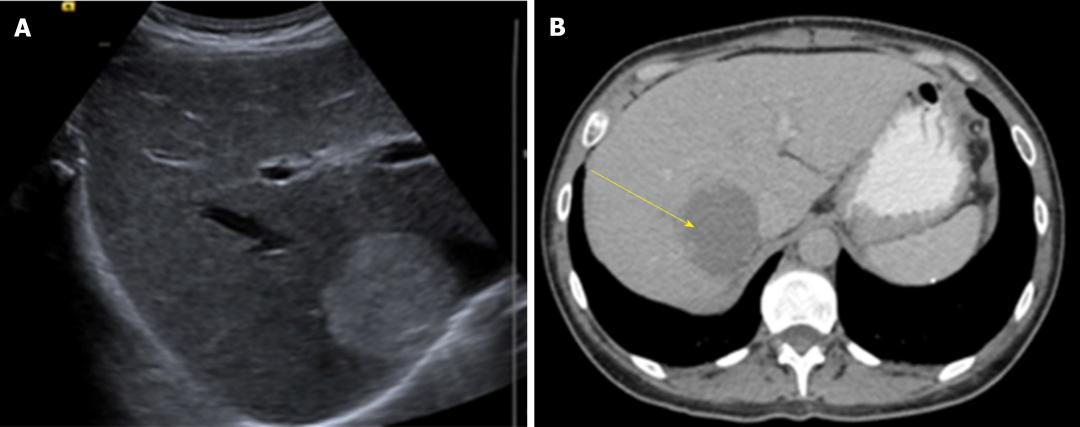

诊断 :HH的诊断目前主要依赖于影像学检查,多种检查手段联合应用可提高诊断准确率。常规首选超声检查,再结合CT、MRI以及数字减影血管造影检查等综合判断。

图1 肝脏超声(A)和腹部CT(B)